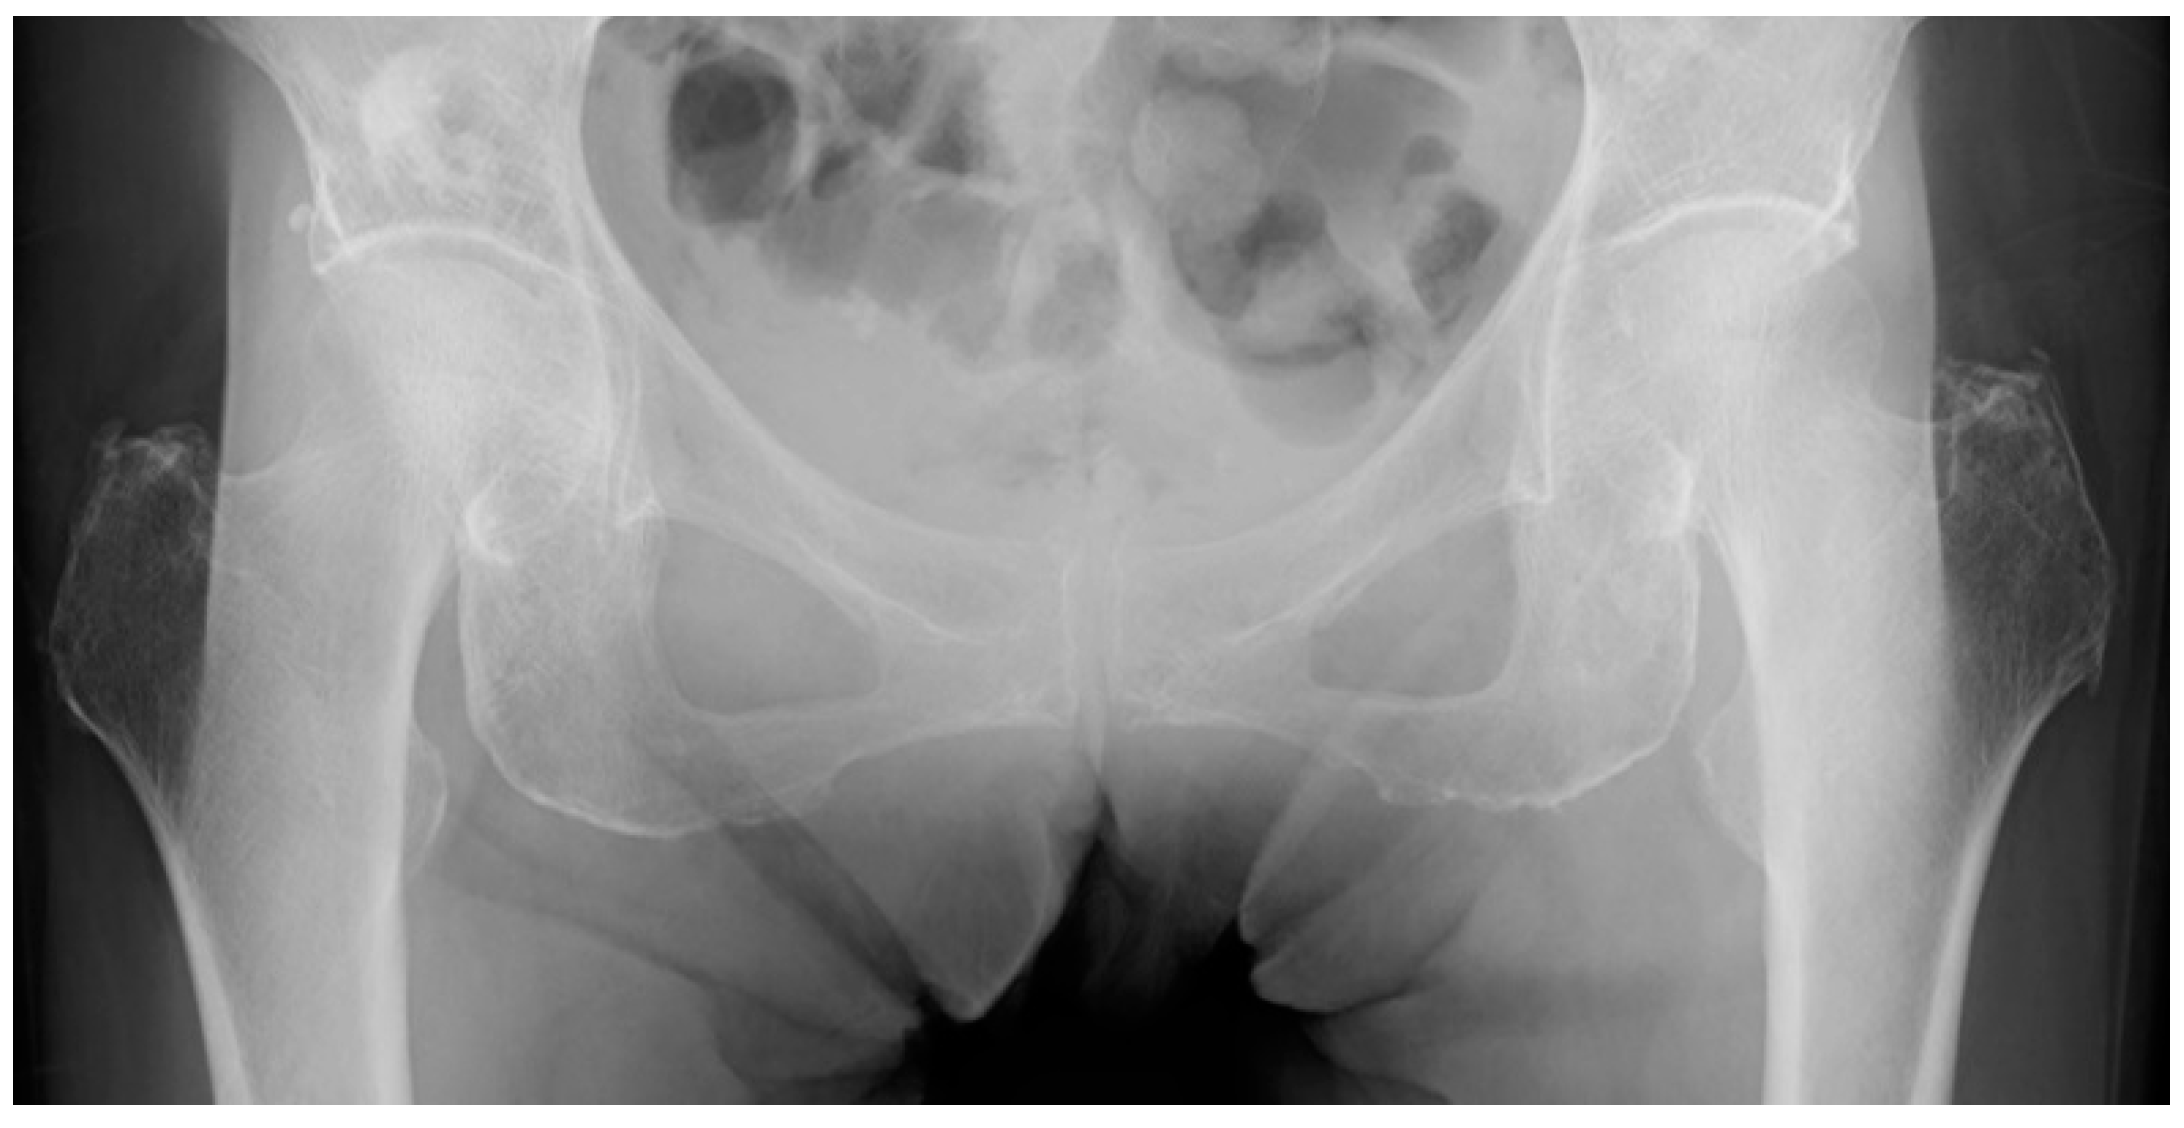

2.2. Patient Selection

2.3. AP Hip Radiographs